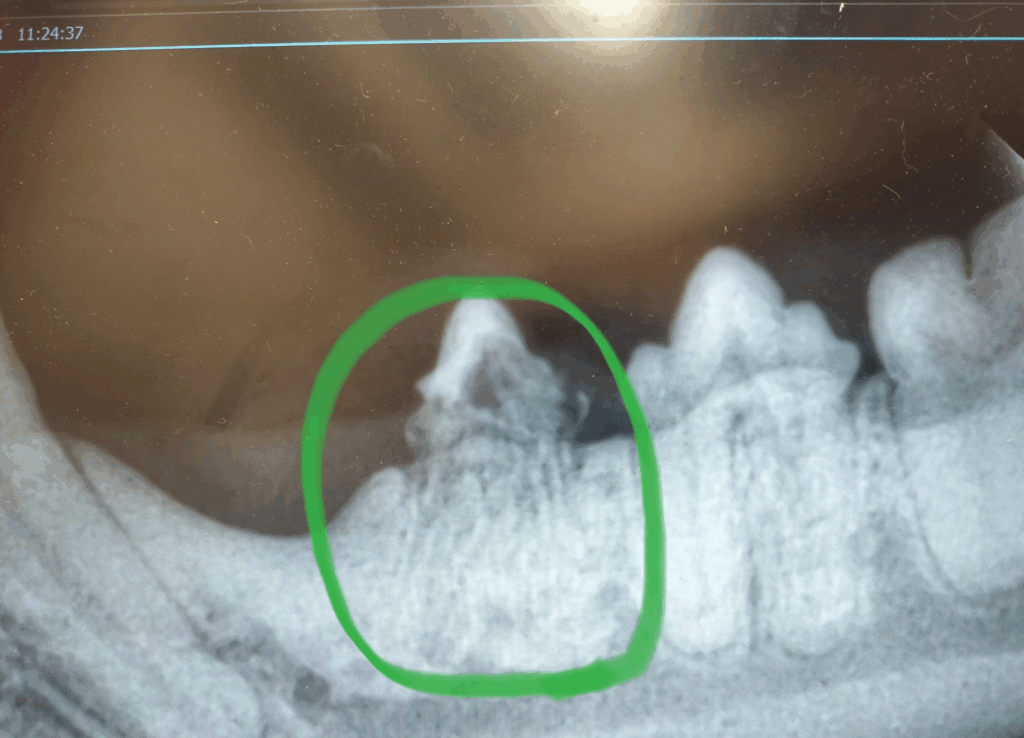

【写真:吸収病巣の歯のレントゲン画像】

こちらは猫ちゃんの吸収病巣のレントゲン画像です。

一見、表面はきれいに見えても、レントゲンで見ると歯の根がぼろぼろに溶けているのがわかります。

このように、肉眼では「歯が少し赤いだけ」と見えることもありますが、実際には歯の内部が完全に崩壊しているケースもあります。